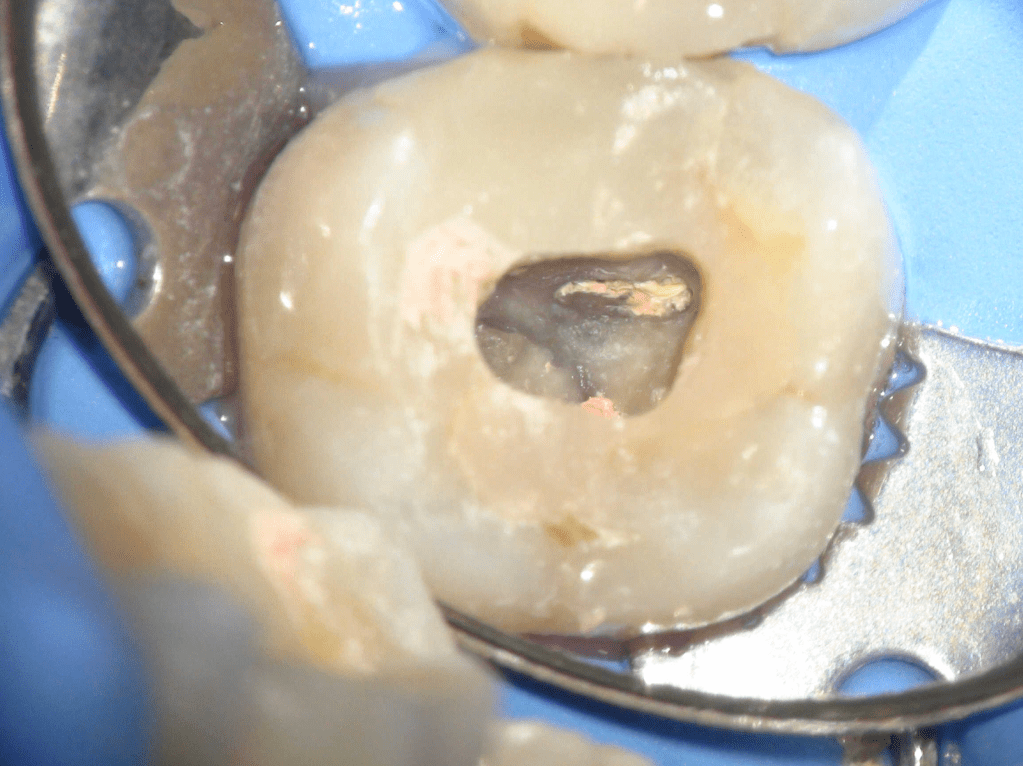

Acceso ultraconservador a través de incrustación reciente